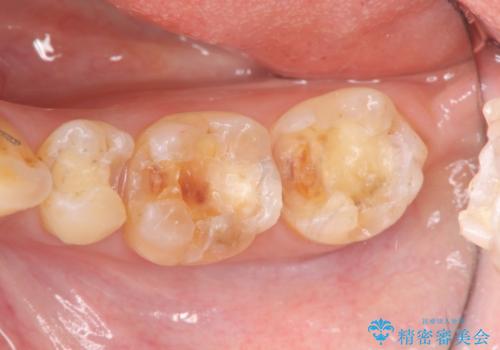

- 他院で銀歯の下部に再発した虫歯の存在を指摘され、精密な治療を求めて来院されました。

銀歯下に虫歯が再発すると神経に近くなり、根管治療を必要とする可能性が高まってしまいます。

健全な歯を削らないように拡大鏡下で丁寧に虫歯を除去することで神経を温存し精密なセラミック治療を行うことができました。

虫歯の再発を防ぐには、細菌の侵入・繁殖を許さない高度な適合レベルと劣化の少ない材質を用いた修復治療を行うことが大変重要です。